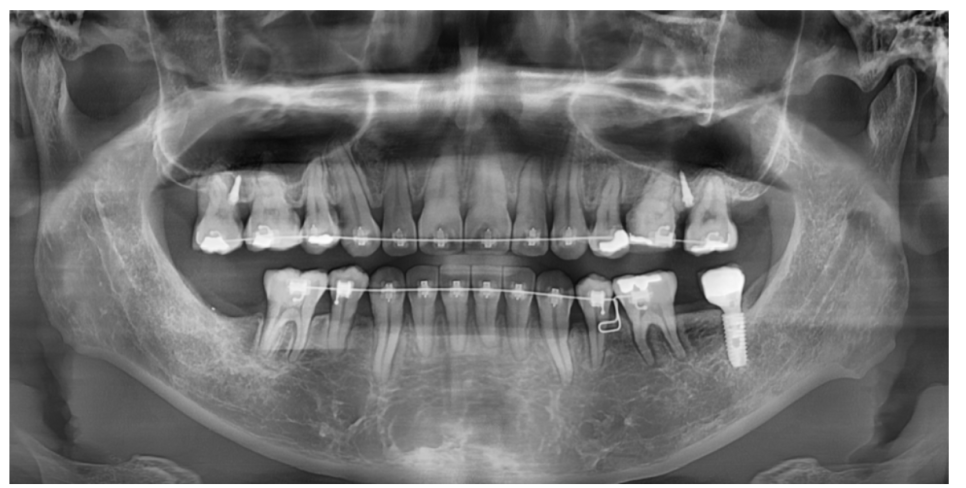

250116

250304

250509